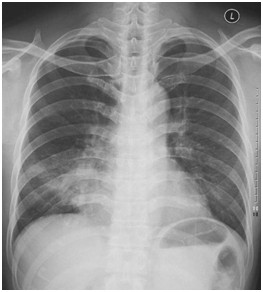

临床助理医师实践技能考试模拟试题:“ X线-正常胸片 ”影像诊断!

2022-03-29

2022年临床助理医师实践技能考试影像诊断模拟题(2分)

临床助理执业医师实践技能考试第一站例题:影像诊断